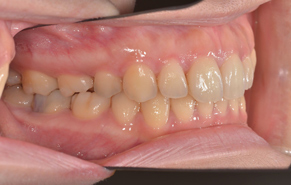

前歯のガタガタと口元の突出感を改善したいと言われました。

口元の突出感の改善には抜歯が必要となり、上下左右の計4本を抜歯しています。治療後は抜歯した隙間を使って配列して、閉じることで口元を入れました。